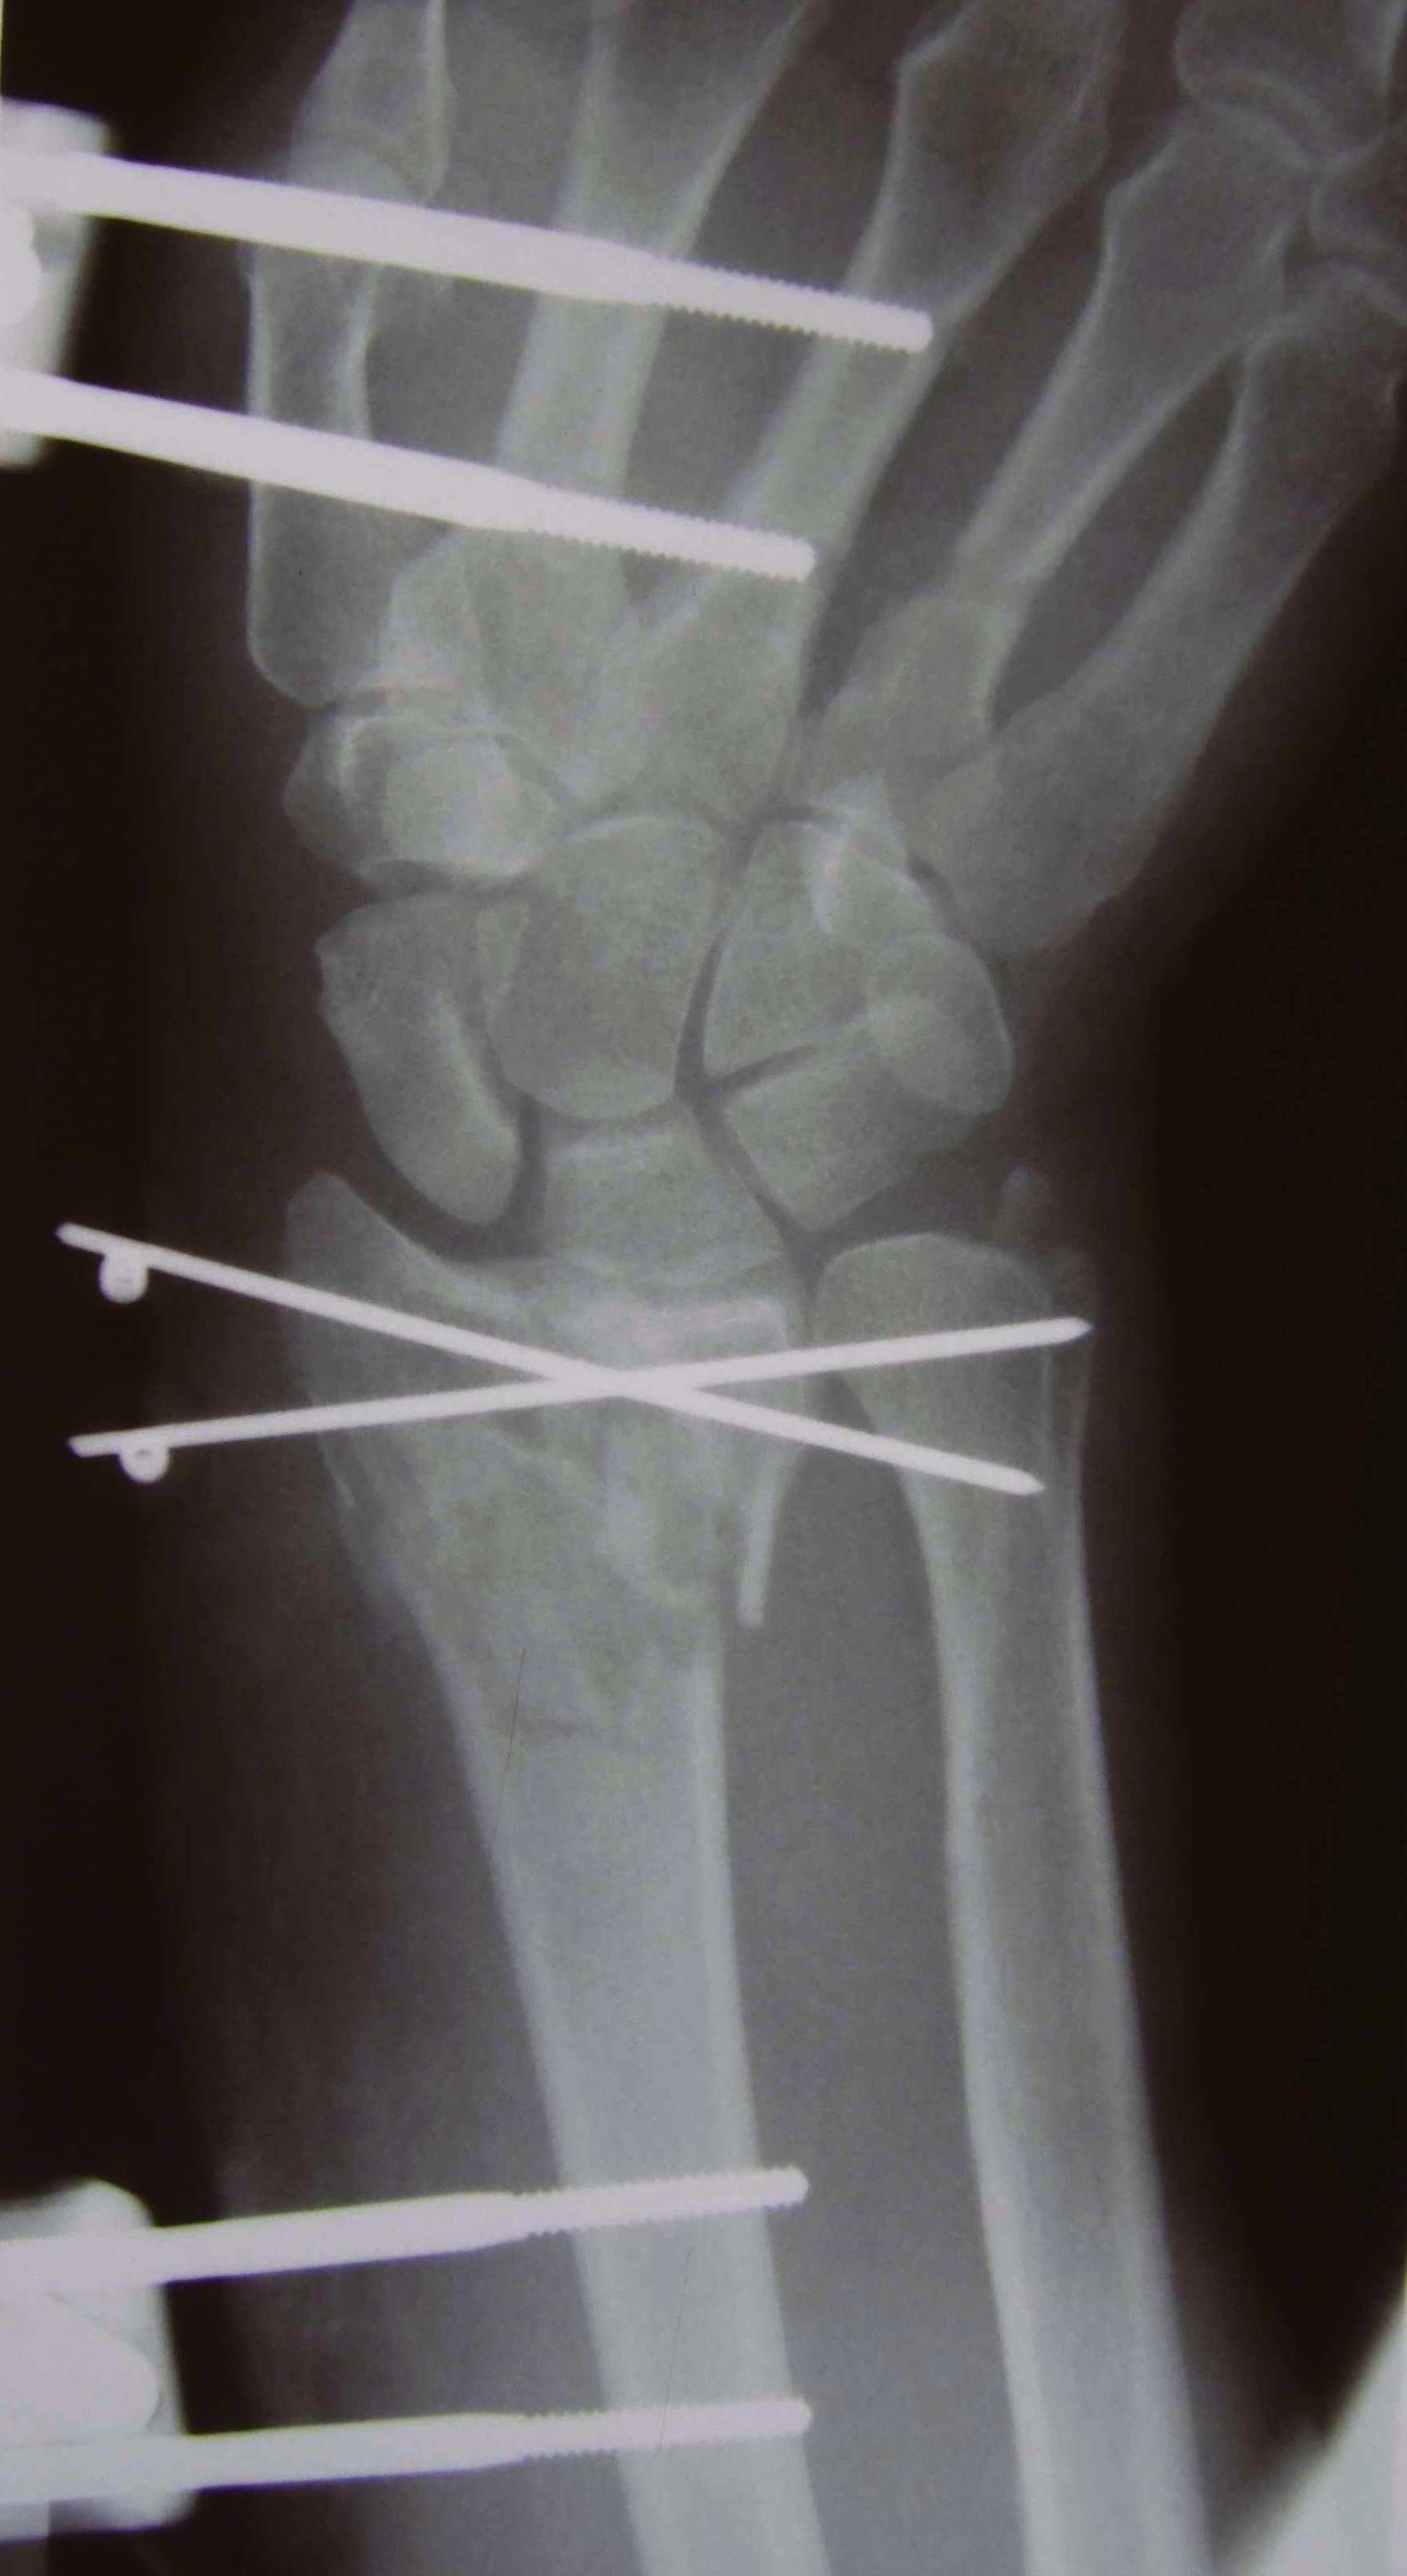

Percutaneous K Wire

Issues

Increased pin site infections

No early immobilization

Reduce fracture under anesthesia and fluoroscopy

Radial K wire

- through radial styloid

- can make small incision / blunt dissect to protect branches SRN

- cross fracture site and engage other cortex

- 1.6 or 2 mm K wire

Dorsal K wire Kapandji technique

- percutaneous by hand into fracture site

- tilt distally to reduce dorsal displacement of distal fragment

- drive into proximal radius and engage volar cortex